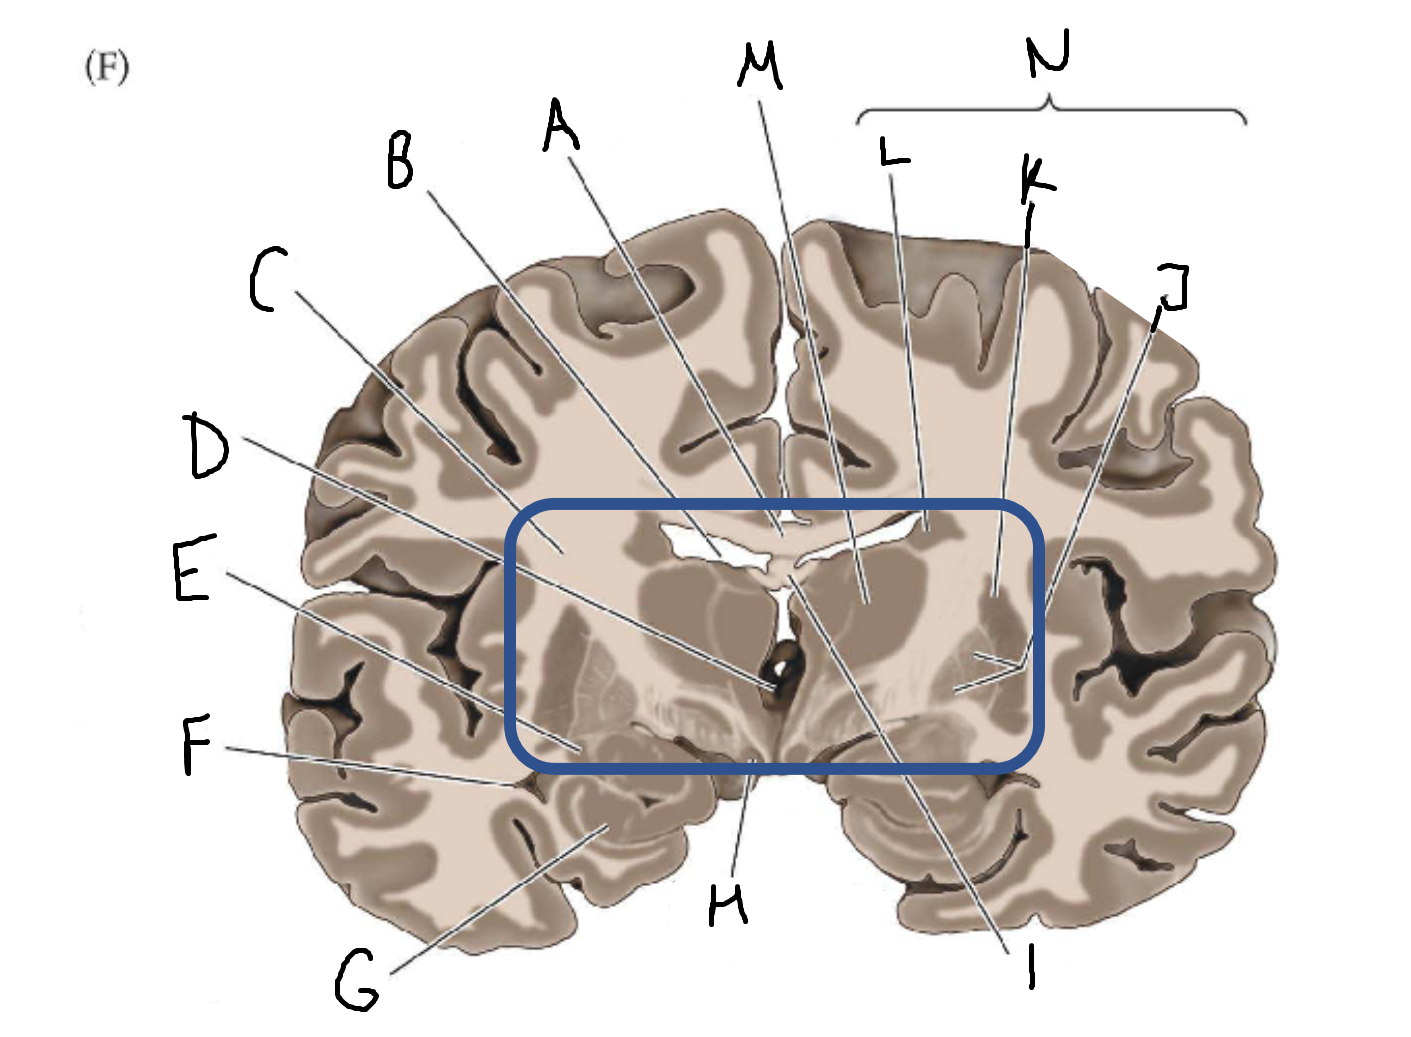

A

corpus callosum

B

lateral ventricle

C

internal capsule

D

third ventricle

E

tail of caudate nucleus

F

lateral ventricle

G

hippocampus

H

mammillary body

I

fornix

J

globus pallidus

K

putamen

L

caudate

M

thalamus

N

basal ganglia